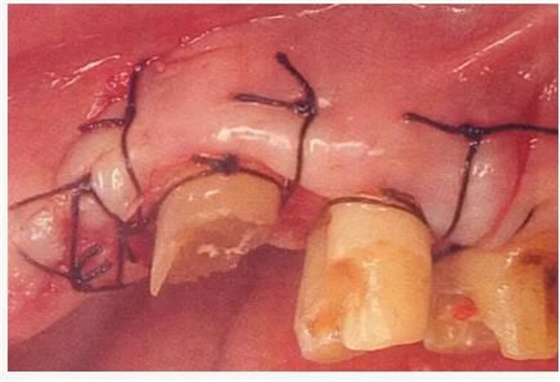

使齦瓣上端與牙槽嵴頂一致,通過(guò)骨膜縫合進(jìn)行固定。